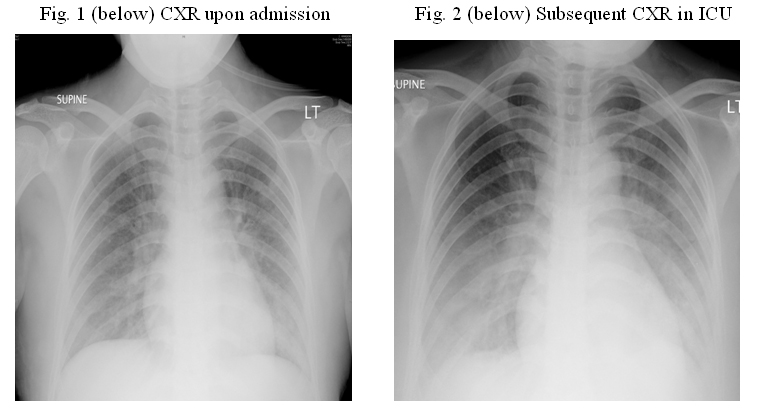

Case 2 (Presented by Dr. Johnny Chan, Department of Medicine, Queen Elizabeth Hospital) A 48 year-old previously healthy saleslady, developed fever, cough with yellowish sputum, sore throat, chills and rigors on 8 July 2009. Being a chronic smoker of 1 packet per day for 20 years, she had no recent history of travel or contact with patients with known Human Swine Influenza (HSI). Despite medications offered by 3 different general practitioners in the following week, which included paracetamol, non-steroidal anti-inflammatory agents and cough mixtures, she felt increasingly unwell with progressive dyspnoea and eventually attended emergency room one week after symptom onset. Upon admission, her SaO2 was only 85% in room air and she was running a fever of 38.5C. Blood tests revealed lymphopenia, thrombocytopenia and mildly deranged liver function tests. She was promptly transferred to the Intensive Care Unit (ICU) on the same day of hospital admission. Initial CXR revealed consolidations over right upper, right middle, and left lingular lobes. (Fig. 1) The tests for HSI subsequently turned out to be positive. Apart from profound type I respiratory failure that required mechanical ventilation with high PEEP, high PiO2 and NO therapy, she also developed shock with the requirement of high dose inotropes. Apart from administration of antibiotics like Tazocin, Klacid and Vancomycin (subsequently Linezolid), she was given Tamiflu 150mg twice daily, acetylcysteine, anti-oxidant therapy and corticosteroid of a physiological dose in ICU. Nebulized Zanamivir (Relenza) had also been administered. Bronchoscopic findings were essentially normal, while CT thorax (Fig. 2) revealed extensive consolidations in both lungs, predominantly in the lower lobes. She was eventually able to be weaned off from mechanical ventilation and discharged back to the general ward after almost 3 weeks’ stay in ICU. She was subsequently transferred to Kowloon Hospital for a short period of rehabilitation.